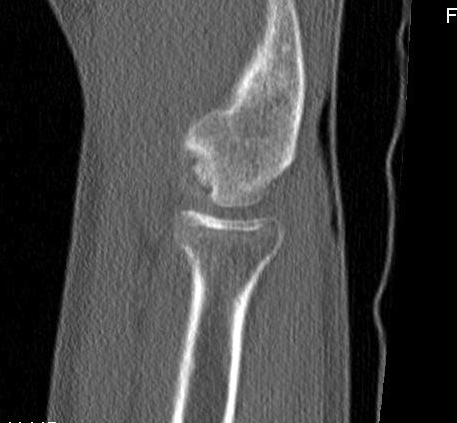

CT

Locations

Central - lateral wall intact, contained, easier to manage

Lateral wall - uncontained lesion

Lateral capitellar OCD Central contained capitellar OCD

Sizing

< half diameter radial head

> half diameter radial head